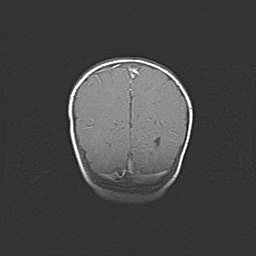

Лейкомаляция с кистозно-глиозной дегенерацией головного мозга.

Возраст: 2 месяца 25 дней

Вес: 6400 г

Окружность головы: 40 см

Срок гестации: 41 неделя

Лейкомаляцию относят к ишемически-гипоксическим повреждениям головного мозга, диагностируемым у новорожденных. При лейкомаляции в головном мозге обнаруживают очаги некроза, возникшие после тяжелой гипоксии и нарушения кровотока. В процессе морфогенеза очаги проходят три стадии: 1) развития некроза, 2) резорбции и 3) формирования глиозного рубца или кисты. Перивентрикулярная лейкомаляция (ПЛ) встречается примерно в 12% случаев среди новорожденных, обычно – у недоношенных детей, причем, частота ее зависит от массы, с которой младенец появился на свет. Наибольшее число малышей страдает лейкомаляцией, если масса при рождении 1500-2500 г.